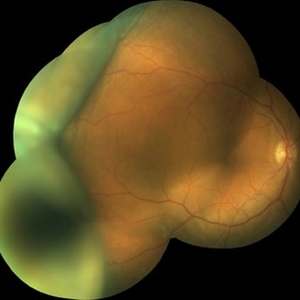

Idiopathic Uveal Effusion Syndrome

Resolved on own in a few months; was taking PO NSAIDS.

Photographer: Kristin Konecki, OcuSight Eye Care Center, Rochester, NY

Condition/keywords: idiopathic uveal effusion syndrome, NSAIDs